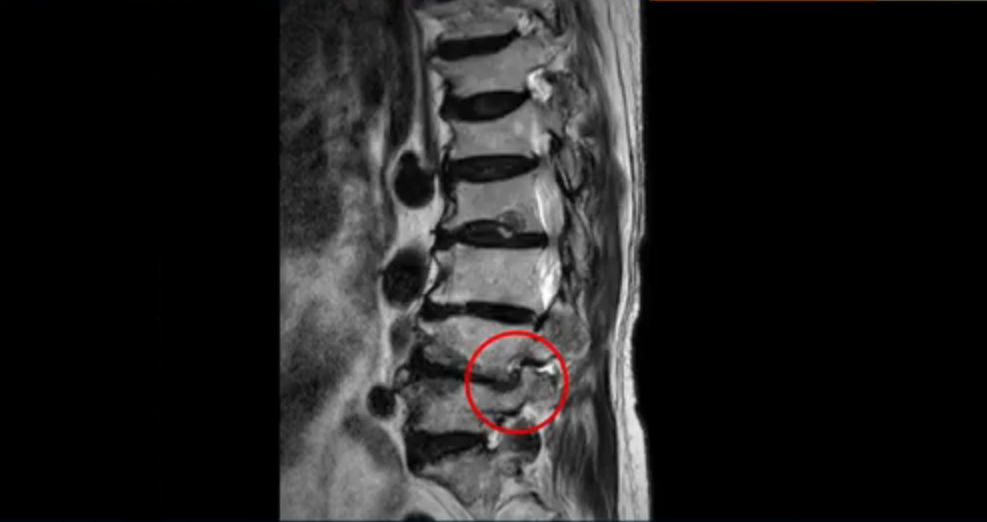

또한 척추뼈 여러 개가 압박 골절과 변형으로 찌그러져 있고

골다공증도 심하시고 보시다시피 근육량이 너무 적습니다. 근육이 정상적인 분들과 비교해보면 근육이 얼마나 적은지 알 수 있습니다.

이렇게 근육도 적고 뼈가 약하신 분들 게다가 여러 마디가 안 좋은 분들은 수술하면 결과가 안 좋을 가능성이 매우 높습니다. 그래서 지방의 척추 병원과 서울의 한 최상급 대학병원에서도 수술을 안 받는 게 좋다, 수술한다 해도 위나 아래가 무너질 수 있다고 들으셨습니다.